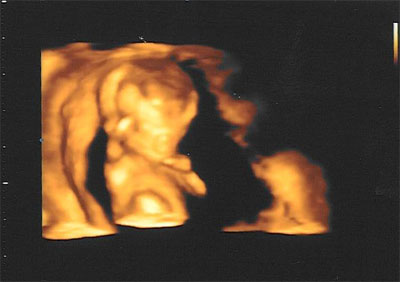

Táááárámmmm!!!

Íme a kis Gubacsunk!!

CRL:60,4

BPD:16,1

NT:1,3

Down:1:25612

minden szupi!!!!!! Kőzápor volt! :D :D :D

kaptunk felvételt is a kis ficánkáról! OOOOlyan édes!! :oops: :oops: